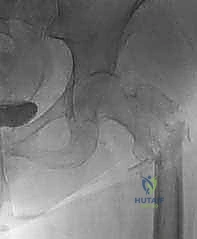

مرض السرطان النقيلي في العظام (Bone Metastasis) هو حالة سريرية متقدمة تنتشر فيها الخلايا السرطانية الخبيثة من ورم أصلي (أولي) نشأ في عضو آخر من الجسم (مثل الثدي، الرئة، البروستاتا) وتنتقل عبر مجرى الدم أو الجهاز الليمفاوي لتستقر وتنمو داخل نسيج العظام. هذه الحالة شائعة جداً في مسار الأورام الخبيثة، حيث تؤثر على أكثر من نصف حالات السرطان المتقدمة.

يعتبر مفصل الورك، وخاصة الثلث العلوي من عظم الفخذ (Proximal Femur) ومنطقة الحُق (Acetabulum) في الحوض، من أكثر العظام تعرضاً لهذه النقائل، حيث يمثل منطقة الورك وحدها حوالي 25% إلى 30% من جميع النقائل العظمية في الهيكل العظمي البشري.

- الأشعة السينية العادية (X-rays): الخطوة الأولى والأساسية. تظهر تدمير العظم (الآفات الحالّة) أو زيادة الكثافة غير الطبيعية (الآفات التكوينية).

- التصوير المقطعي المحوسب (CT Scan): يوفر صوراً ثلاثية الأبعاد تفصيلية للعظام. يعتبر الأداة الأهم لتقييم مدى تدمير العظم القشري (الطبقة الخارجية الصلبة) وتخطيط حجم ونوع المفصل الاصطناعي بدقة.